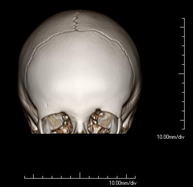

- TC Cráneo

Prueba radiológica que consiste en obtener imágenes del cráneo de alta definición anatómica (tronco cerebral, cerebelo, cerebro, calota craneal, etc.), mediante el empleo de un equipo de TC (Tomografía Computarizada).Indicaciones: traumatismos, cefalea, trastornos de la memoria, pérdida de fuerza súbita en una extremidad o mitad del cuerpo. - TC Cuello